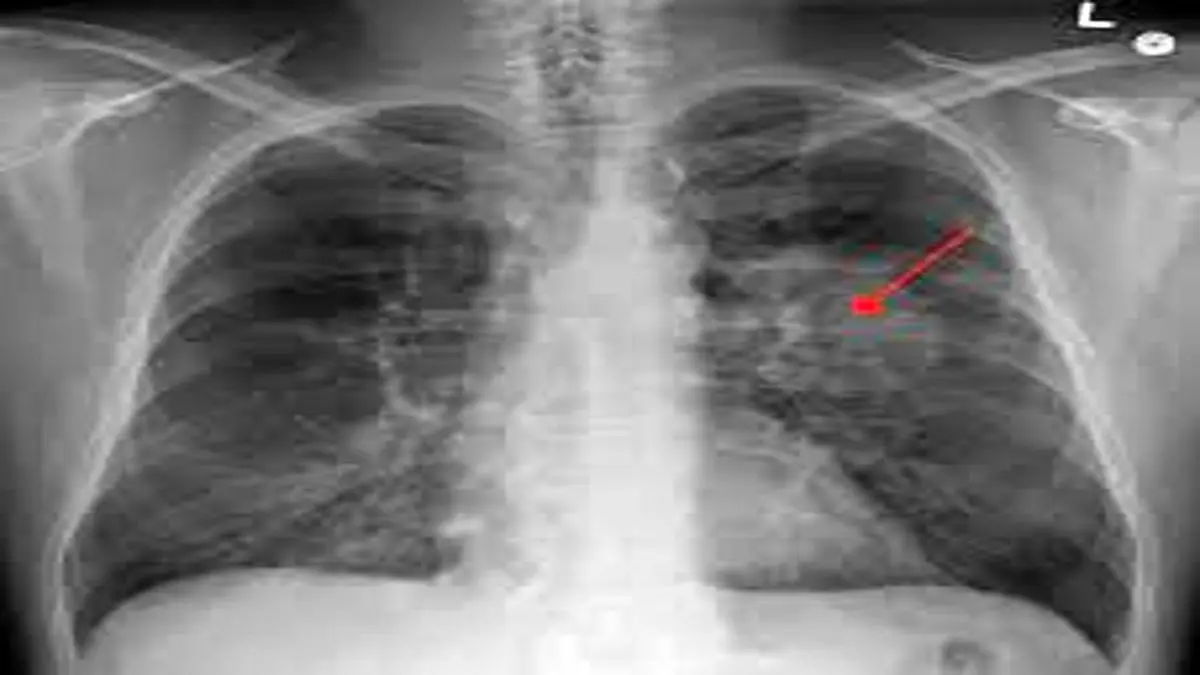

سرطان ریه یکی از عوامل اصلی مرگ و میر ناشی از سرطان در سراسر جهان است و سالانه بیش از دو میلیون نفر در جهان به این بیماری مبتلا می‌شوند. اکثر کسانی که دچار سرطان ریه می‌شوند سابقه مصرف سیگار دارند اما در حدود ۱۰ تا ۲۰ درصد مبتلایان هیچ‌گاه سیگار نکشیده‌اند. سرطان ریه در غیر سیگاری‌ها بیشتر در زنان و در سنین پایین‌تر نسبت به سیگاری‌ها رخ می‌دهد.

در این مطالعه بزرگ اپیدمولوژیک، محققان برای درک تغییرات ژنومی ایجاد شده در غده‌ها و بافت طبیعی، به توالی یابی کامل ژنوم ۲۳۲ فرد غیرسیگاری پرداختند. این افراد که عمدتا اروپایی تبار بودند به سرطان کارسینوم ریه سلول-غیرکوچک دچار شده بودند. این نوع سرطان که حدود ۸۰ تا ۸۵ درصد سرطان‌های ریه را تشکیل می‌دهد شایع‌ترین نوع سرطان در بین افراد غیر سیگاری است.

در این افراد ۱۸۹ تومور "آدنوکارسینوما" (adenocarcinomas) که شایع ترین نوع سرطان ریه است یافت شد. همچنین ۳۶ تومور کارسینوئید(carcinoids) و هفت نوع تومور از انواع مختلف دیگر در این بیماران دیده شد. بیمارانی که تحت بررسی قرار داشتند هنوز درمان خود را شروع نکرده بودند.